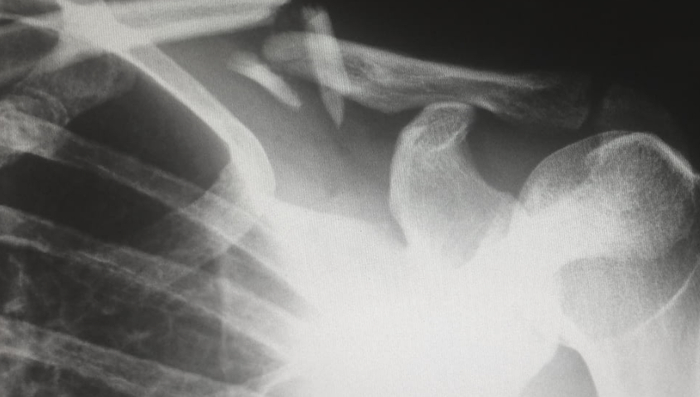

仅仅2年时间左右,人工关节、创伤、脊柱,一个接一个,骨科几乎成为集采最为彻底的高值耗材领域。

国采效应,威力凶猛!继去年人工关节从万元时代迈入千元时代、创伤产品“九折甩卖”之后,骨科厂商将再次同台竞技上,依旧由降幅定输赢!

在7月11日发布的脊柱国采1号文中,根据手术类型、手术部位、入路方式等,囊括进了14套脊柱系统(详情见文末),相比征求意见稿,将脊柱用骨水泥单独列出,更符合市场情况。

有业内人士表示,这14套系统,几乎是“不留死角”,意味着所有脊柱产品都要被集采到!